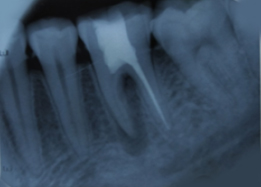

Immediate Post-Surgical IOPAR